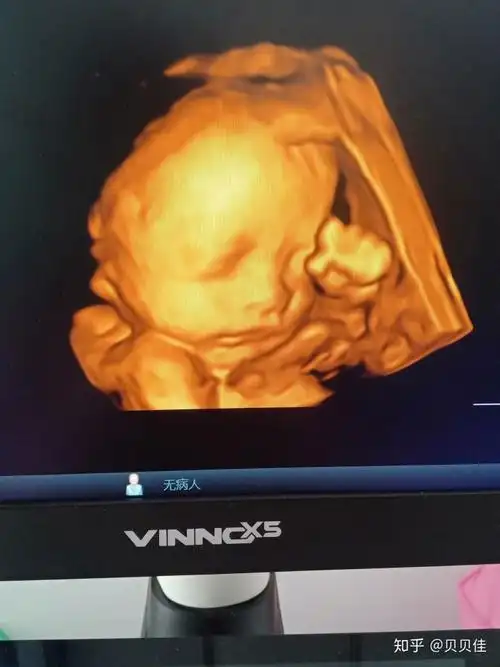

四维彩超看到可爱的她正在揉眼睛